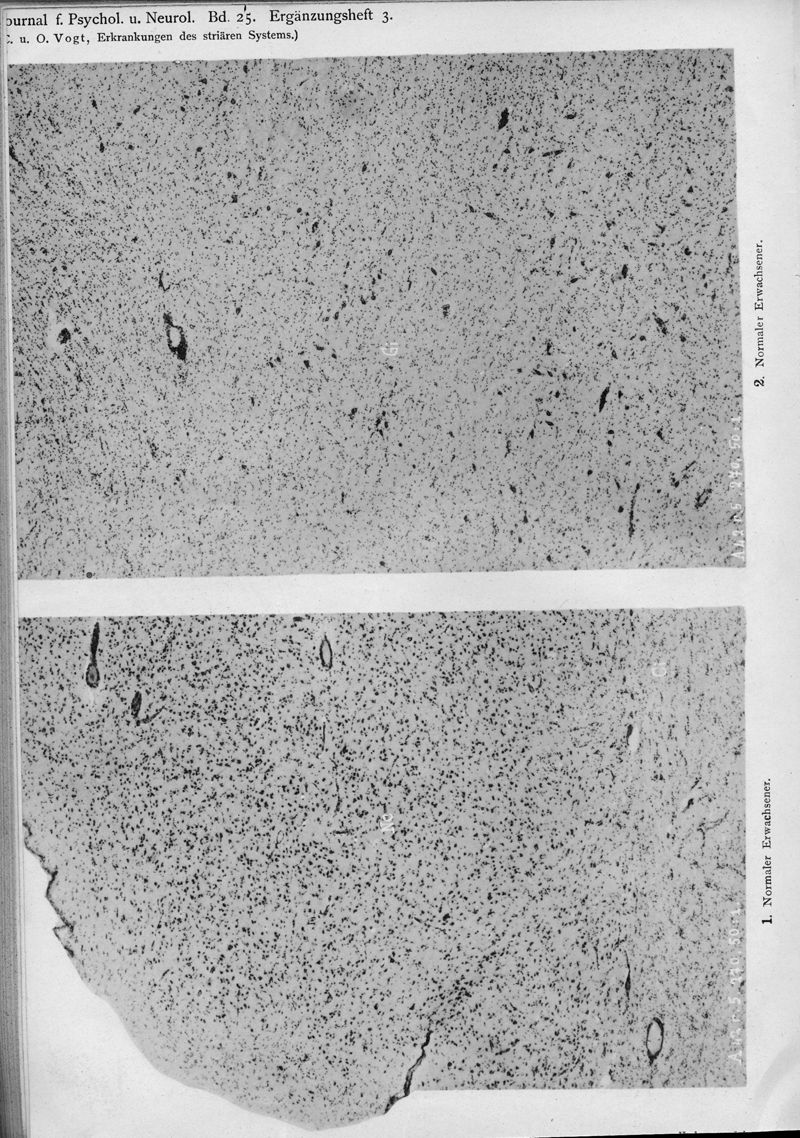

VOGT, Cécile / VOGT, O.

In : Journal für Psychologie und Neurologie,

1920, Vol. 25, pp. 627-846